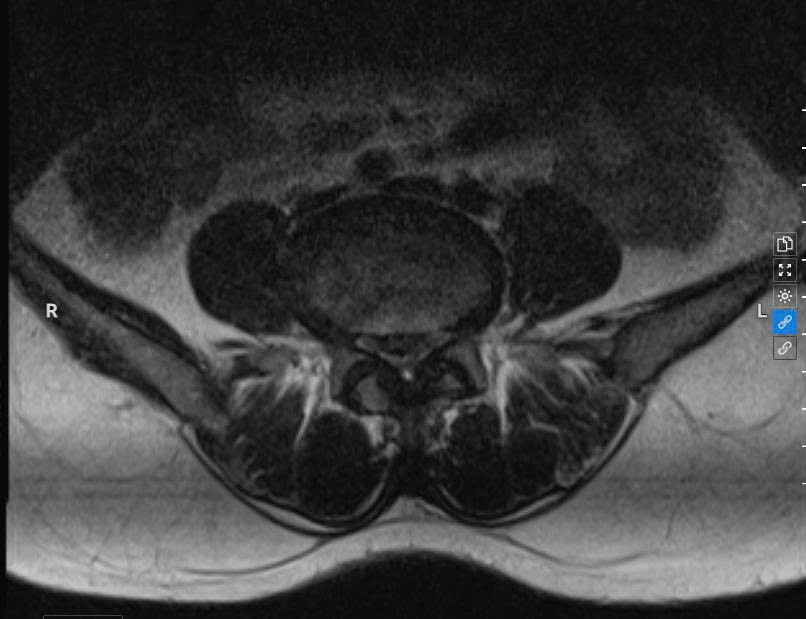

Khi đến khám và thực hiện chụp MRI cột sống thắt lưng tại Bệnh viện A, các bác sĩ Khoa Ngoại Chấn thương chẩn đoán bệnh nhân T. bị thoát vị đĩa đệm L4-5, L5-S1 và có chỉ định nhập viện phẫu thuật nội soi cột sống hai cổng để lấy nhân đệm, giải phóng chèn ép thần kinh.

Hình ảnh chụp MRI cột sống thắt lưng bị thoát vị đĩa đệm L4-5, L5-S1 của bệnh nhân T.